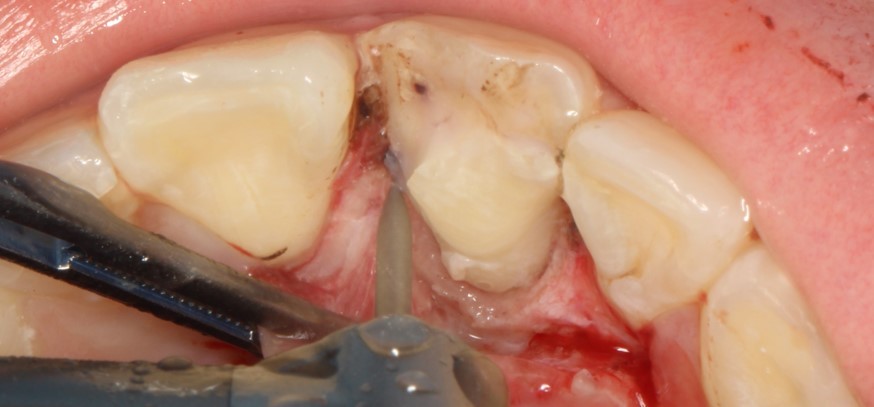

На данной фотографии продемонстрирована припасовка осколка зуба. Далее зуб и осколок был вычищен и адгезивно подготовлен к фиксации.

После фиксации отломка были убраны излишки жидкотекучего композита

Далее была восстановлена медиальная стенка зуба до ушивания десны.